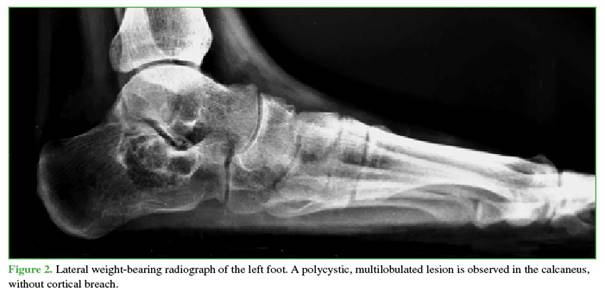

The lateral weight-bearing radiograph of the foot revealed a multilobulated, polycystic lesion confined within the cortices of the left calcaneus (Figure 2). Non-contrast MRI showed an expansile, eccentric lesion with well-defined margins, multilobulated morphology, and internal fluid-fluid levels, measuring 3.3 cm in anteroposterior and transverse dimensions and 2.7 cm in cephalocaudal extension (Figure 3).